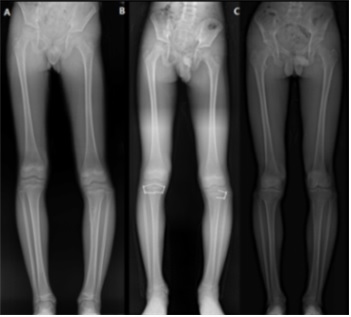

무릎 주변에 단발성 골연골종을 가진 환자 83명을 분석한 결과, 83명 중 8명(9.6%)에서 하지 변형이 관찰됐다.

하지 변형이 발생한 8명 중 3명은 하지 부동(다리 길이 차이), 2명은 O다리 및 X다리, 3명은 하지 부동과 O·X다리가 모두 발생한 것으로 나타났다.

또한, 하지 변형이 발생한 환자들은 모두 ‘무경성’ 골연골종을 가진 것으로 확인됐다. 골연골종은 줄기가 없는 납작한 모양의 ‘무경성’과 줄기가 있는 ‘유경성’으로 구분되는데, 연구팀에 따르면 무경성인 경우 유경성일 때와 비교해 하지 변형 발생 위험이 24배 높았다.